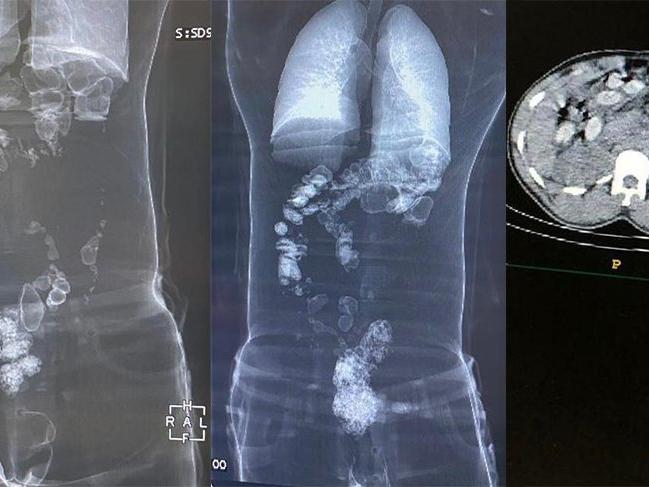

Hastanede çekilen tomografide şahısların mide ve bağırsaklarında uyuşturucu madde ele geçirildi. Diyarbakır Emniyet Müdürlüğünden yapılan açıklamada, "Hastanede çekilen tomografide şüpheli S.E.Z.’den 2 kapsül halinde 74,36 gram metamfetamin, 18 kapsül halinde 172,8 gram eroin maddesi, şüpheli Y.Y.B’den 3 kapsül halinde 115,05 gram metamfetamin, 39 kapsül halinde 351,18 gram eroin maddesi, şüpheli A.S.G.’den 2 kapsül halinde 75,83 gram metamfetamin maddes olmak üzere toplamda 7 kapsül halinde 265,24 gram metamfetamin maddesi, 57 kapsül halinde 523,9 gram eroin maddesi ele geçirilmiştir. Şüpheliler çıkarıldıkları mahkemece tutuklanarak cezaevine sevk edilmiştir" denildi.